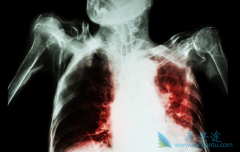

肺癌,是目前全人类的杀手。在我国肺癌是发病率和死亡率双高的恶性肿瘤。从19世纪起,人类陆续开始尝试用手术、放射、化疗等方式来治疗肺癌,但是效果并不理想。大量临床数据表明,肺癌早期的5年生存率高达70%~80%以上,而晚期肺癌的5年生存率为5%以下。 ...

肺癌患者往往发现的时候已经是中晚期了,早期肺癌症状类似感冒咳嗽,很容易被患者忽视,不治疗身体也没出现大的问题,就没在意,当几年后突然检查时,医生告知肺癌晚期。那么, 晚期肺癌能治吗 ?当然是可以的,肺癌晚期可以选择外科的治疗,比如放射性 ...

现在大家都谈癌色变,一旦得了癌症就觉得离死不远了。其实,随着检查手段和医疗技术的发展,很多癌症现在都是可以治愈的,就算是一些不能治愈的癌症,也可以通过一系列的治疗实现带瘤生存。以肺癌为例,如果患者能够在早期发现病情,一般手术加上一些辅 ...